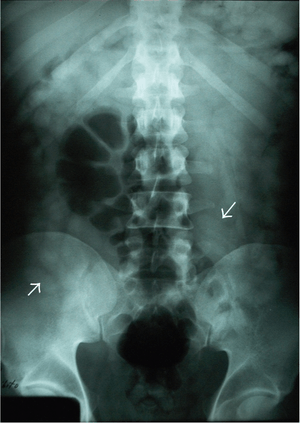

Body-packing with multiple foreign bodies ("balls" of hashish) on KUB